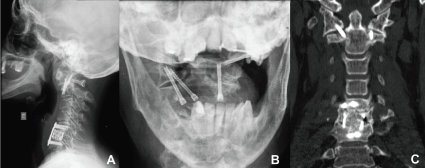

Atlantoaxial fixation in RA is proposed to those patients with atlantoaxial instability that present an established or imminent neurological deficit, and for those with untreatable cervical or occipital pain. Atlantoaxial arthrodesis in patients with RA provides better results for cervical spine function, with an improvement in VAS scores for neck or shoulder pain or stiffness, but little improvement in pain or numbness of the lower extremities [23]. It is usually performed by a dorsal approach, and may use transarticular screws [24], sublaminar wiring or, more recently, the Harms-Goel technique, which associates screws in lateral masses of C1 to screws in C2 pedicle, connected by plates or rods. Goel, et al. introduced an innovative concept for surgically handling rheumatoid instability of CVJ [25]. Based on the principle that retro-odontoid pannus results of regional ligament slackness, they advocate that a bilateral facet distraction between C1-C2 associated to the placement of stainless steel joint spacers in distracted facets, with or without this segment instrumentation, allows the stabilization of atlantoaxial subluxation and, at the same time, the restoration of lateral masses height, providing simultaneous vertical stability and basilar invagination resolution. That way, by means of an atlantoaxial distractive arthrodesis, it's possible to treat atlantoaxial instability, basilar invagination and medullary compression simultaneously through retro-odontoid pannus. In early published papers, due to the use of stainless steel materials, the postoperative evaluation through MRI of pannus reduction and spinal cord alterations was difficult. By modifying the technique, we now came to use titanium materials for both lateral mass screws in C1 and pedicular screws in C2, as well as titanium mesh spacers, which provide a better radiologic control of soft parts through NMR [26]. Most recently, aiming to avoid subsidence due to the use of titanium mesh spacers and a better control of osseointegration, we've been using Polyetheretherketone (PEEK) cages in this technique, with consolidation rates in 100 percent of patients and absence of subsidence [27]. Figure 2 and Figure 3 illustrate the case of a patient with RA and basilar invagination associated to subluxation in C4-C5 and subaxial myelopathy. A posterior atlantoaxial distractive arthrodesis was performed with the Goel technique to treat basilar invagination and anterior corpectomy of C4 and C5 with C3-C6 arthrodesis (Figure 2 and Figure 3).

Figure 2: Profile radiography (A), CT with sagittal reconstructions (B and C) and NMR sagittal acquisition (D) preoperative of a patient with RA Ranawat IIIa, illustrating the association of basilar invagination and instability with subaxial myelopathy. View Figure 2

Figure 3: Profile radiography (A) CT sagittal reconstructions (B and C) and coronal (D) postoperative of the same patient, illustrating the surgical treatment performed with posterior atlantoaxial distractive arthrodesis through Goel technique for the treatment of basilar invagination, and anterior decompressive corpectomy with arthrodesis for the treatment of subaxial instability. View Figure 3